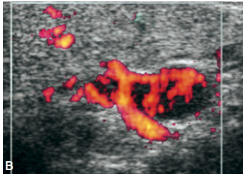

• *Hypoechoic solid lesion**

• *Hypervascular**

• Arch

• Feeding vessel